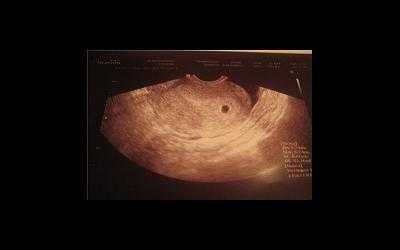

Фото УЗИ плода при беременности 4-5 недель

Самый ранний срок, на котором можно разглядеть с помощью трансвагинального УЗИ плодное яйцо в полости матки - это 30-й день гестации, или 4-5 акушерских недель беременности. Уровень ХГЧ крови при этом должен быть не менее 1000 мЕд/мл. В это время ещё не видно ни эмбриона, ни желточного мешка. При визуализации двух плодных яиц можно утверждать, что это дихориальная многоплодная беременность. При визуализации одного плодного яйца можно утверждать, что это монохориальная беременность. Но на этом сроке мы ещё не можем сказать сколько эмбрионов находится в каждом плодном яйце. Кроме того, во время однократного УЗИ мы ещё не можем сказать, прогрессирует ли данная беременность, так как у эмбриона ещё нет сердцебиения. Средний внутренний диаметр (СВД) плодного яйца на этом сроке 2-10 мм.

В заключении будет указано: Маточная беременность малого срока.